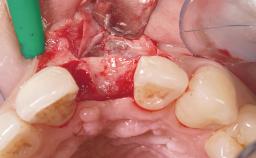

A 39-year-old male patient presented with a chief complaint of discomfort and gingival discoloration around his maxillary left central incisor. He was in good general health and was a non-smoker. His past dental history was significant because of the traumatic fracture of tooth 21 in a sporting accident at age 13. Initial dental treatment included endodontic therapy and a full-coverage restoration. The patient became symptomatic 5 years later, when structural failure of the tooth resulted in the dislodgment of the crown. Endodontic retreatment, apical surgery, and post-and-core restoration were performed.

| Bone Augmentation | Horizontal|Staged |

| Augmentation Materials | Xenogenous|Membrane |